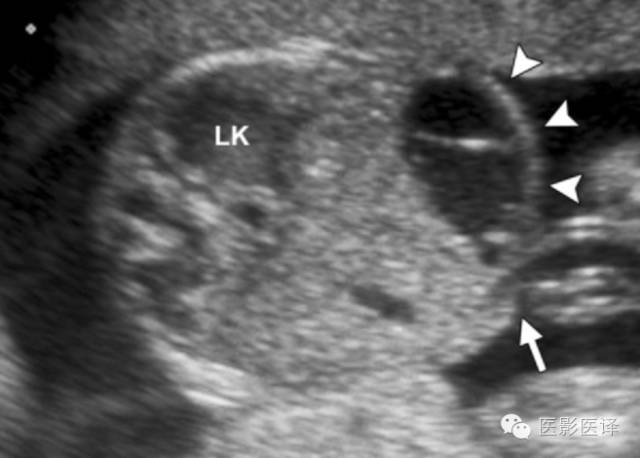

多囊性肾发育不良

MCDK(多囊性肾发育不良)是一种非遗传性肾发育不良。MCDK的超声表现包括多发的肉眼可见的、不相通的无回声囊肿替代肾组织,并严重地扭曲肾脏外形(图9)。一个多囊性肿块可依据它位于靠近脊柱肾窝的位置来确定其肾脏起源。肾盂和肾盏无法辨别,几乎总能观察到肾盂输尿管交界处闭锁。大多数MCDK病历是单侧的(80%),受累肾脏无功能。MCDK通常随着时间的推移渐退化;在9个月到10年完全退化率为19%-74%。肾脏初始长度6.2厘米或更少可以很好地预测受累肾脏完全退化。

图9.MCDK.胎儿的彩色多普勒超声横断位图像显示一个多囊性占位(箭),邻近脊柱和主动脉(Ao)。这是MCDK的典型影像表现。